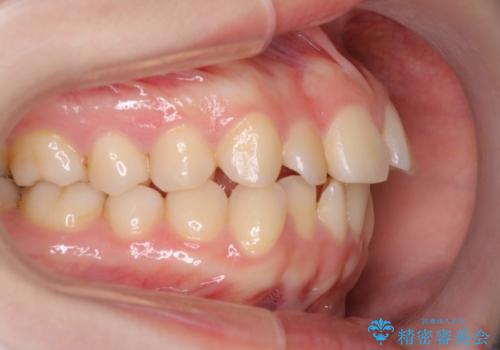

インビザラインによるガタつきの矯正治療 シンプル・短期間

- 非抜歯、IPR+拡大によるマウスピース矯正を計画した。

一見前歯のガタつきだけのように見えても、そのガタつきの根本的な原因が奥歯の位置であったりすると、マウスピースの枚数がそれなりに多くなり、治療に時間がかかることもあります。